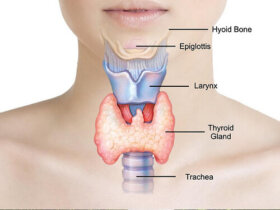

갑상선은 신체의 작은 부분에 불과하지만 가장 중요한 기능 중 하나인 신진대사를 조절하는 역할을 한다. 만약 갑상선의 기능이 저하되었다면, 심박수가 떨어지고 에너지 수치가 떨어지며 운동이나 육체활동을 해도 더 적은 에너지를 태울 것이다. 오늘 이 글에서는 갑상선 자연 치료법을 소개한다. 갑상선에 대해서…